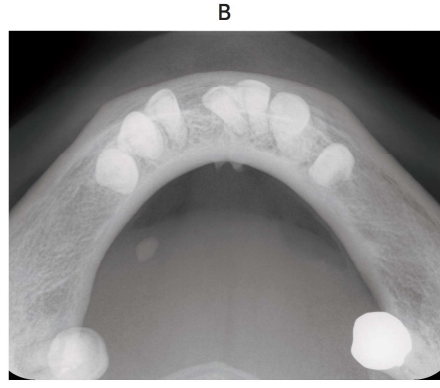

118回 A-70

下部の疼痛を主訴とする患者のエックス線画像(別冊No. 22A、B)を別に示す。

追加する画像検査と目的の組合せで正しいのはどれか。 1 つ選べ。

解答:a

解説:

下顎左側に唾石がある。

位置がはっきりとわからないのでCTが必要。